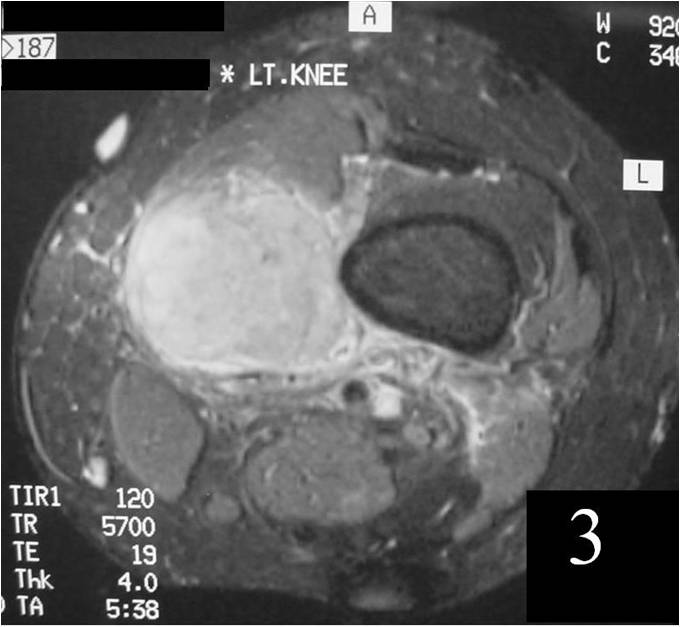

MRI

Nonspecific nonfatty mass (Fig. 2,3)

Large heterogeneous mass (Fig. 4, 5, 6)

Isointense to skeletal muscle on T1W

Usually heterogeneous on T2W SE